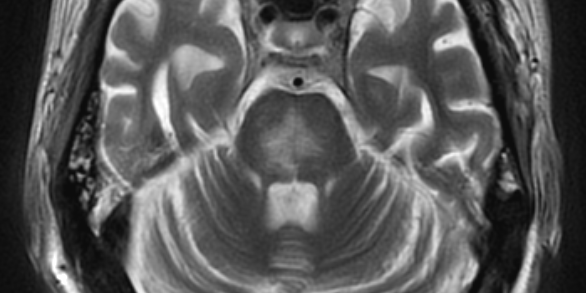

Cerebellar Atrophy

Do you know the common substances that cause cerebellar atrophy?